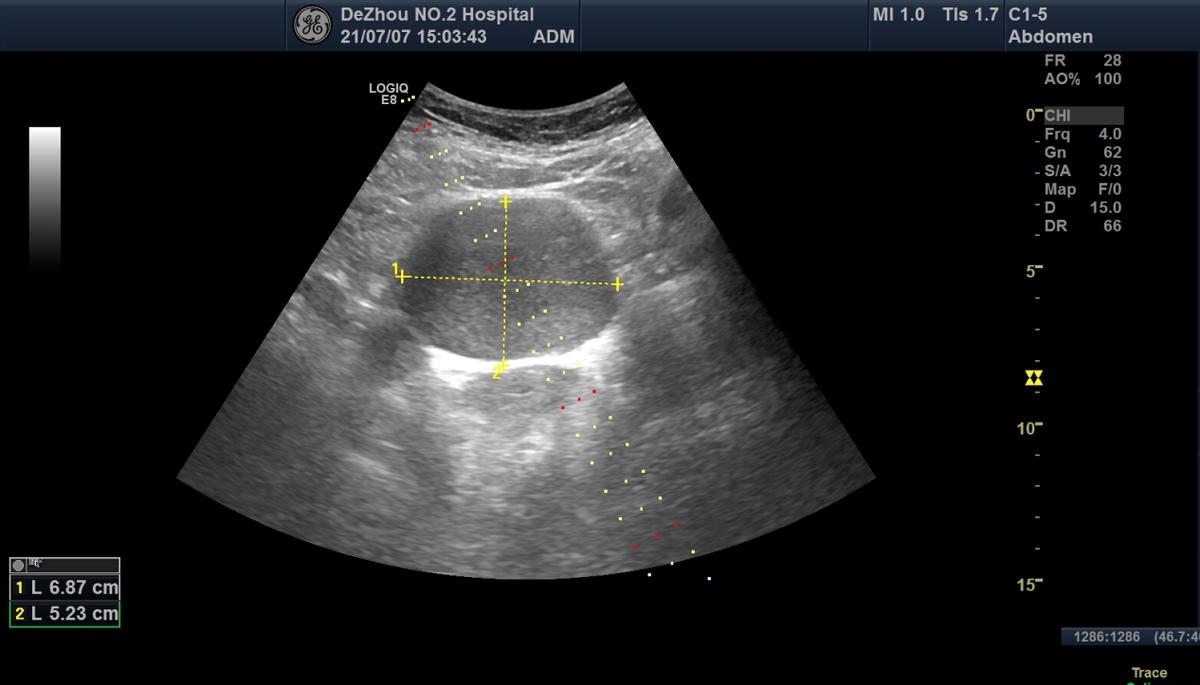

超声检查发现:子宫大小形态及内部回声正常,右侧附件区可见6.9×5.2cm大小的囊性肿物,与右侧卵巢相连,呈圆形,壁厚,表面光滑,内部透声差,可见细密的点状回声,囊内无分隔,后方回声有增强,肿物可随体位移动至膀胱上方。超声提示:右侧卵巢囊性肿物 考虑子宫内膜异位囊肿(巧克力囊肿)。

超声确定穿刺路径